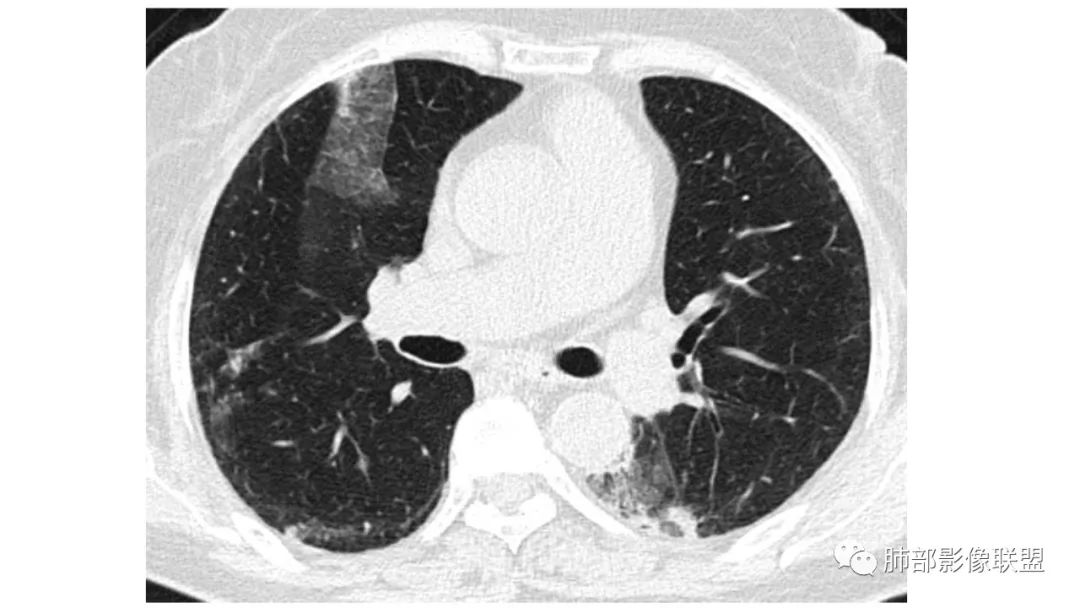

二、肺炎型

2、病灶常有一个主病灶,常位于下肺。后沿气道播散为多发病灶。

3、重力作用,叠瓦征。近叶间裂因重力效应,呈膨隆改变。

4、增强后不均匀强化,存在低强化区呈弱强化或无强化,因此可见“血管造影征。”血管毛糙与肺炎有统计学差异。

5、支气管粗细不均,呈“枯树枝征”,但与肺炎这一点鉴别不具有统计学差异。可发生支气管扩张

6、空腔形成,部分蜂窝状改变。

8、斑片常伴有结节,边缘清楚GGO或欠清楚。